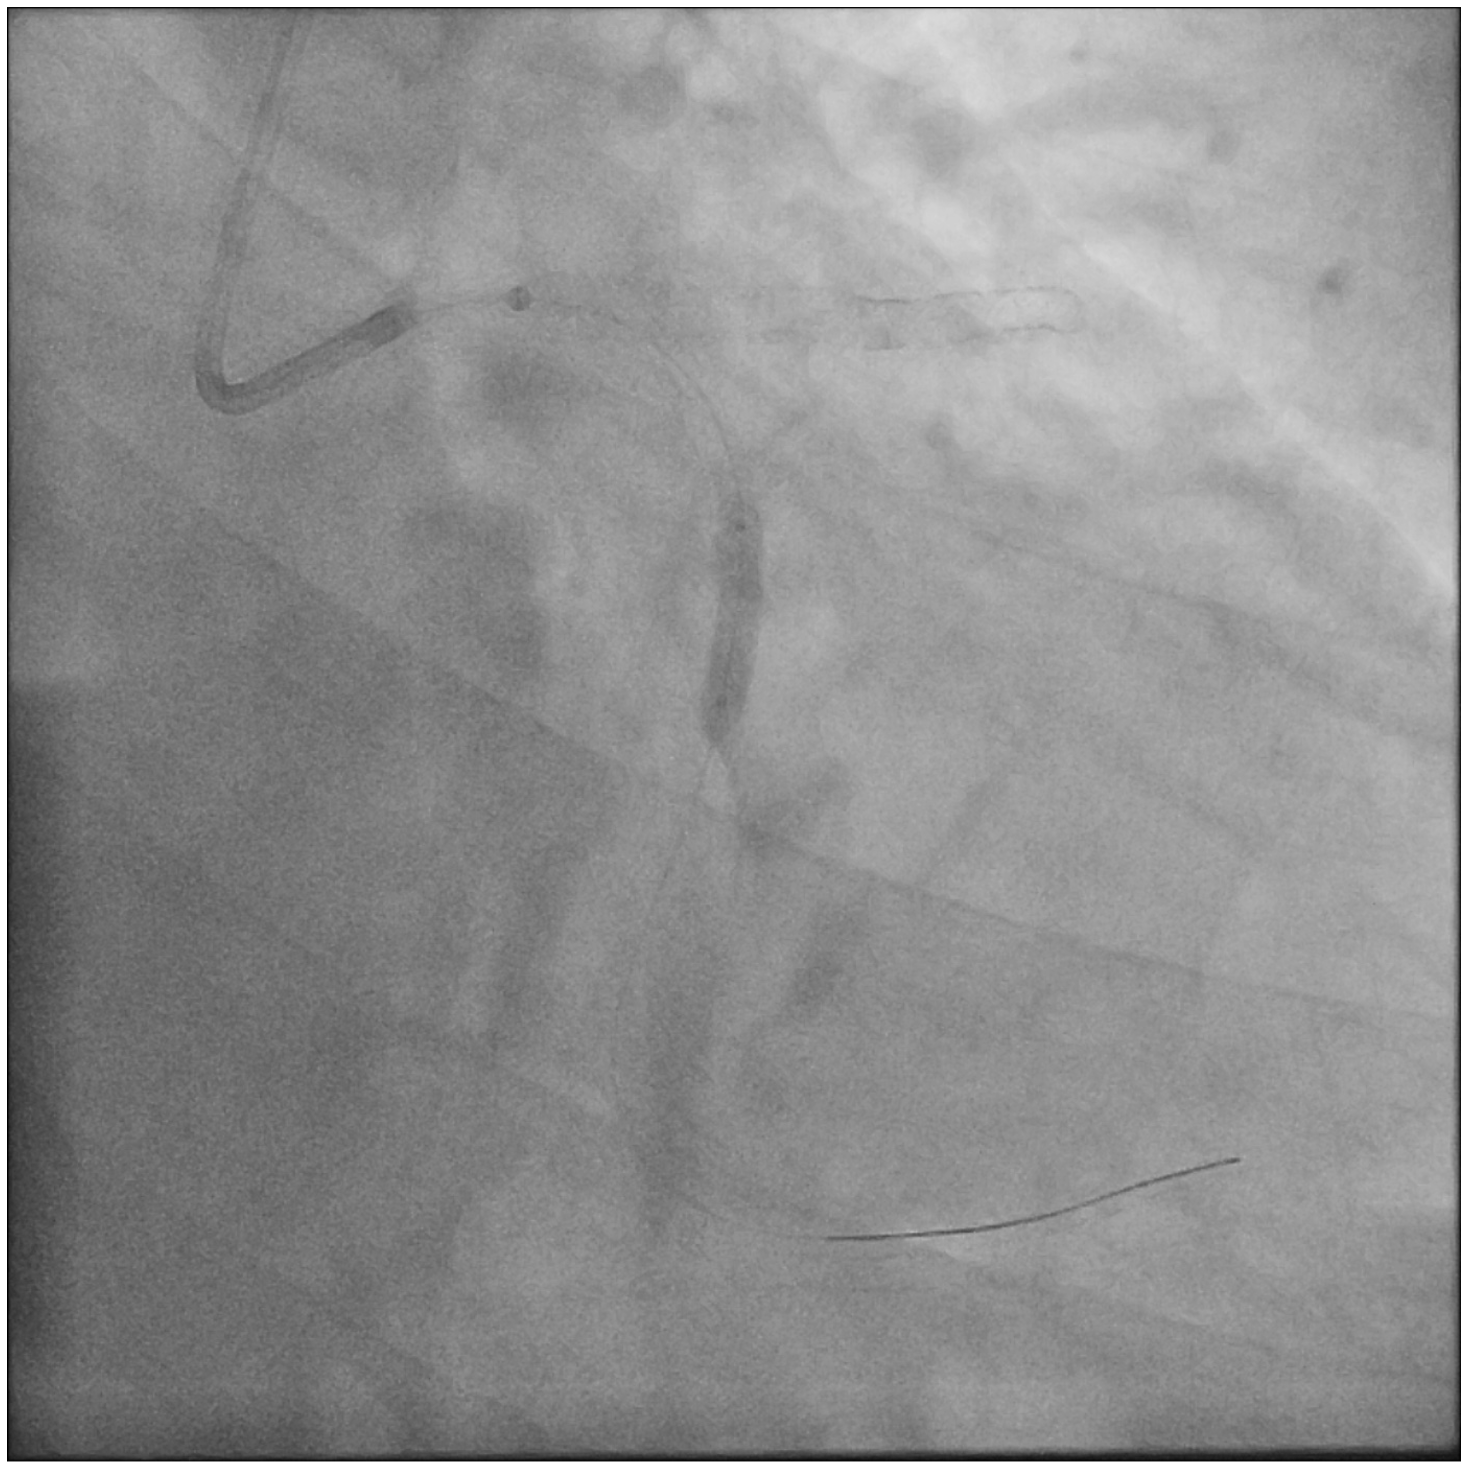

A 71-year-old man who had undergone percutaneous transluminal coronary angioplasty (PTCA) in 2013 was admitted for unstable angina. Coronary angiogram showed 2 de novo lesions at the proximal and distal left circumflex artery (LCX) (Figure 1A). PTCA was performed transradially via a 6-French (Fr) sheath. With a 6-Fr extra-backup 3.5 guide catheter engaging to the left main coronary artery (LM), a 2.5 x 18-mm drug-eluting stent (DES) was delivered to the distal LCX lesion but was inadequate for complete lesion coverage (Figure 1B). During retrieval, the stent was found dislodged at the distal LM bifurcation (Figure 1C).

Distal small balloon retrieval was unsuccessful (Figure 1D). With the help of the Balloon-Assisted Guide-extension (BAG) system, the stent could be optimally positioned at the proximal LCX lesion by forward pushing with a 6-Fr Guideliner V3 catheter (Teleflex) and backward pulling by the small balloon (Figure 1E and F; Video). It was then deployed by sequential balloon dilatation with good expansion (Figure 1G and H). Another 2.5 x 24-mm DES was deployed at the distal LCX, which gave an excellent final angiographic result (Figure 1I and J).